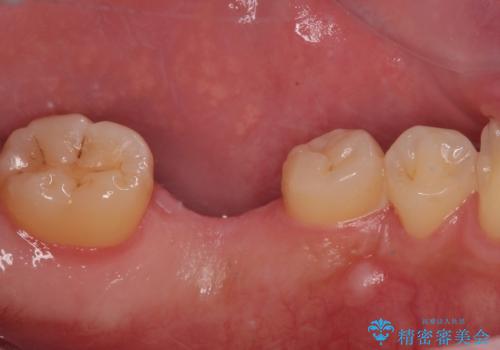

左下の欠損部を長期間欠損を放置していたことで、咬み合う上の奥歯が動いてしまっている状態でした。

インプラント部は埋入とともに仮歯を装着し、同時に上顎奥歯の部分矯正を開始することとしました。

理想的な咬み合わせに改善した上で、インプラント補綴治療を行うこととしました。